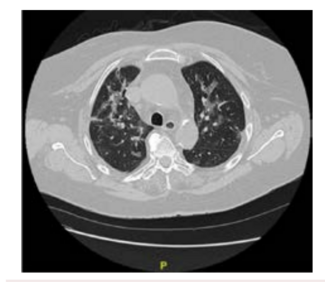

The authors present a case of COVID-19 associated with aortic thrombus in a 62-year-old female patient with comorbidities.